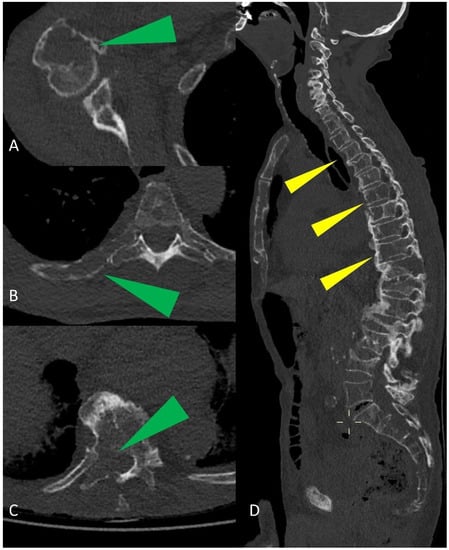

Whole-Body Low-Dose Multidetector-Row CT in Multiple Myeloma: Guidance in Performing, Observing, and Interpreting the Imaging Findings

3. WBLD-CT Imaging Findings and Evaluation

4. Differentiation of Multiple Myeloma and Metastasis